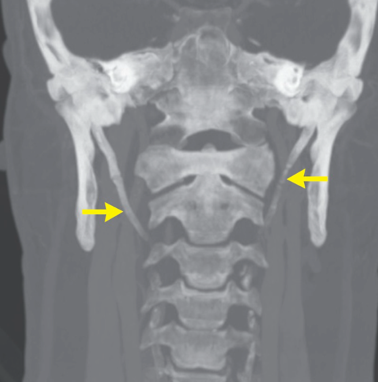

Eagle Syndrome: Elongation of styloid process or ossification of stylohyoid ligament

- Diagnosis: CT with 3D reconstruction (preferred modality), X-ray